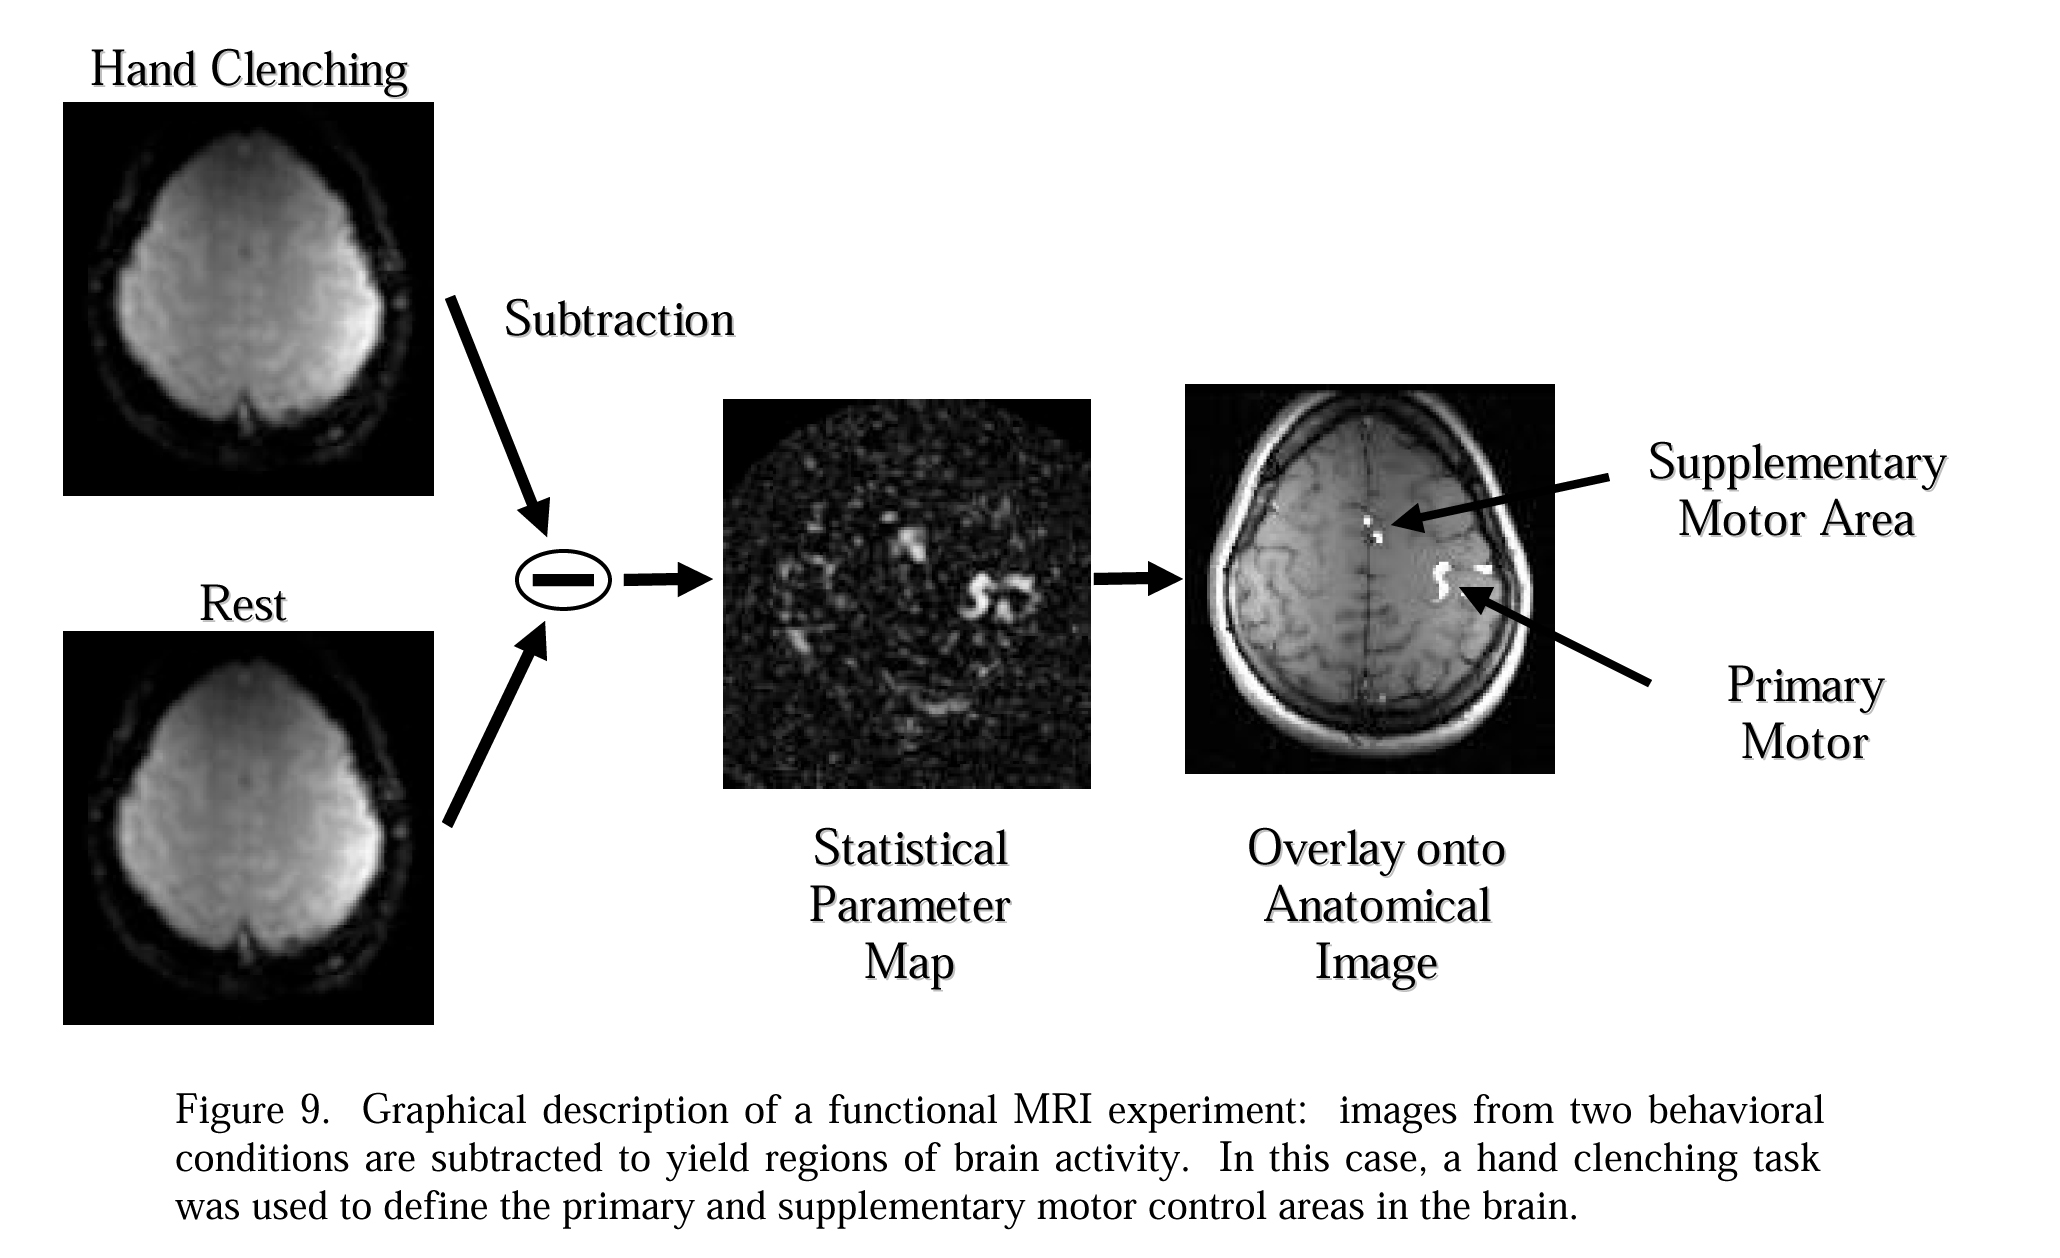

functional magnetic resonance imaging (fMRI)

- Oxy-hemoglobin and deoxy-hemoglobin have different magnetic resonance signals

- Brain areas activated by a specific task utilize O2, then a pulse of O2 comes back and creates an influx of oxy-hemoglobin

- Can repeat task many times over

- Spatial resolution– millimeters

- Temporal resolution– seconds

Note:

fMRI

Note:

Mapping brain activity with fMRI

Note: